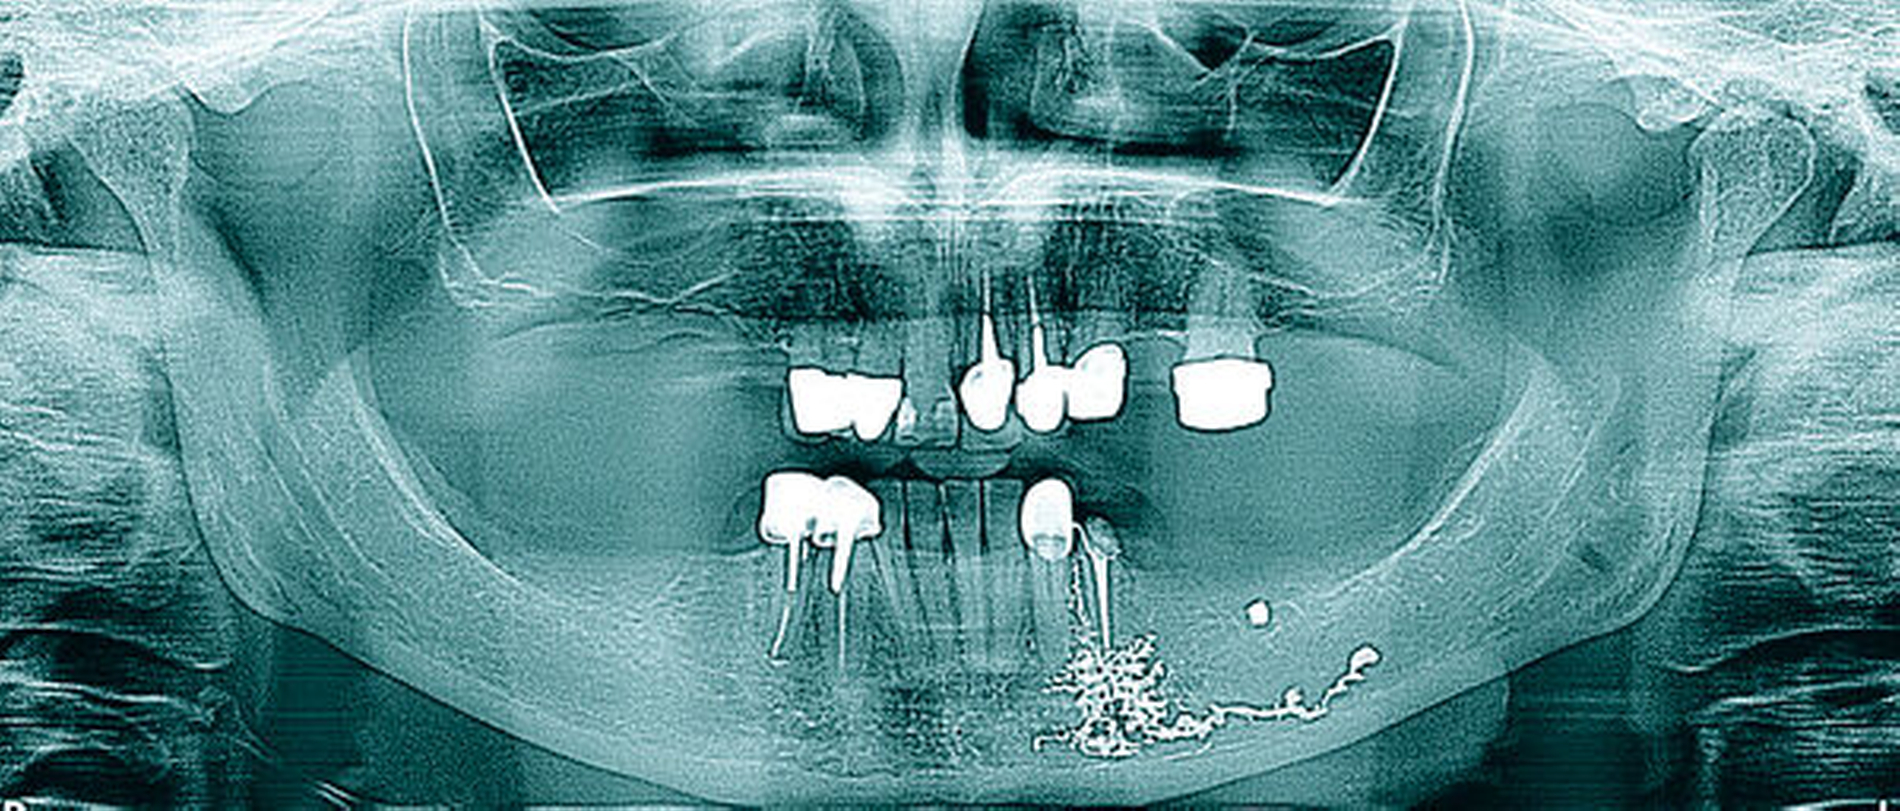

Radiologisch zeigt die erste Panoramaschichtaufnahme die präendodontische Ausgangssituation mit einer metalldichten Verschattung in regio 036. Die postendodontische Panoramaschichtaufnahme stellt die Wurzelfüllung mit dem überpressten Sealer periapikal und in Höhe des Mandibularkanals links dar (Abbildungen 1 und 2).

Zur Beurteilung der Überfüllung wurde alio loco eine DVT erstellt, die den Sealerverlauf in allen Ebenen abbildet. Der Austritt des Sealers nach lingual, nach bukkal und im Mandibularkanal wird hier dreidimensional präzise dargestellt (Abbildungen 3 und 4).